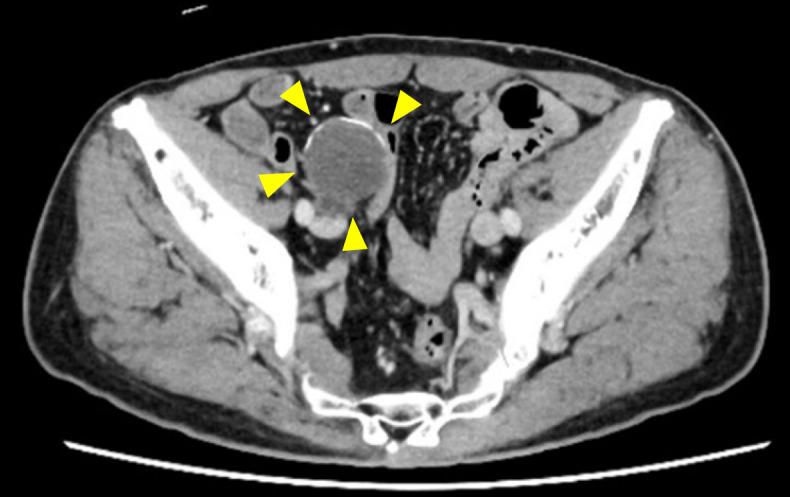

Appendiceal mucinous neoplasms (AMNs) are rare tumors originating from mucin-producing epithelial cells of the appendix. They can exhibit both benign and malignant behavior. They are often incidentally discovered during appendectomy. Clinical presentation ranges from asymptomatic to mimicking acute appendicitis. Histologically, noninvasive AMNs are classified as low-grade AMNs (LAMNs) or high-grade AMNs (HAMNs), whereas invasive tumors are categorized as mucinous adenocarcinomas. Although LAMNs and HAMNs are generally nonmalignant, rupture can lead to pseudomyxoma peritonei (PMP). Surgical resection is the primary diagnostic and therapeutic approach, with intraoperative assessment to prevent rupture. Treatment strategies vary based on findings and include appendectomy, right hemicolectomy, and cytoreductive surgery with hyperthermic intraperitoneal chemotherapy. Histological diagnosis relies on mucin detection, and immunohistochemical markers such as cytokeratin 20 (diffusely positive), cytokeratin 7 (often negative), mucin 5AC, and special AT-rich sequence-binding protein 2 assist in characterization. Molecular profiling frequently identifies , , and mutations. mutations are generally associated with a favorable prognosis, whereas and mutations correlate with poorer survival outcomes. These findings highlight the potential role of molecular profiling in guiding treatment strategies for AMN and PMP.

阑尾黏液性肿瘤(AMNs)是起源于阑尾黏液分泌上皮细胞的罕见肿瘤。它们可表现出良性和恶性行为。常在阑尾切除术中偶然发现。临床表现从无症状到类似急性阑尾炎不等。在组织学上,非侵袭性AMNs分为低级别AMNs(LAMNs)或高级别AMNs(HAMNs),而侵袭性肿瘤则归类为黏液腺癌。虽然LAMNs和HAMNs通常为非恶性,但破裂可导致腹膜假黏液瘤(PMP)。手术切除是主要的诊断和治疗方法,术中需进行评估以防止破裂。治疗策略根据检查结果而异,包括阑尾切除术、右半结肠切除术以及伴有热灌注腹腔化疗的减瘤手术。组织学诊断依赖于黏液检测,细胞角蛋白20(弥漫性阳性)、细胞角蛋白7(常为阴性)、黏蛋白5AC和富含AT序列的特殊结合蛋白2等免疫组化标志物有助于特征描述。分子谱分析常可识别 、 和 突变。 突变通常与预后良好相关,而 和 突变与较差的生存结果相关。这些发现凸显了分子谱分析在指导AMN和PMP治疗策略方面的潜在作用。